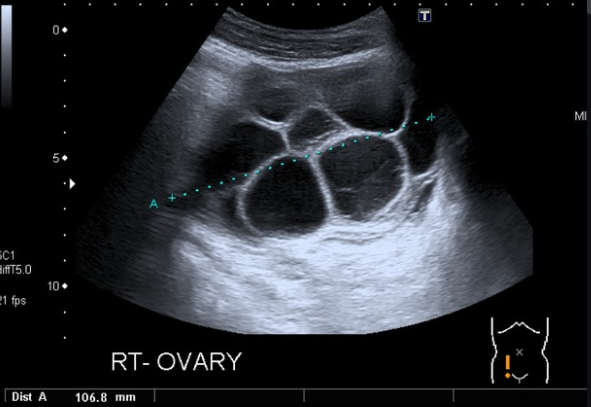

산과력 0-0-1-0인 32세 여성이 최근 4일간 지속된 복부 불편감과 호흡 곤란을 호소하며 내원했다. 환자는 불임 치료를 위해 10일 전에 과배란 유도 치료를 받고 난자 채취술을 시행받았다고 한다. 환자의 혈압은 115/70 mmHg, 맥박은 90회/분, 호흡수는 22회/분, 체온은 36.5℃로 측정되었다. 혈액검사 및 골반 초음파 검사 결과는 아래와 같다. 이 환자에게 가장 적절한 처치는 무엇인가?

Imp: OHSS, ovarian hyperstimulation syndrome

최근 과배란 유도 및 난자 채취 이력이 있는 환자에서 복부 불편감 및 호흡곤란이 발생했으며, 초음파에서 다방성 낭종이 보이므로 보조생식술 관련 합병증인 난소과자극증후군(OHSS)을 의심할 수 있다. OHSS는 난소가 커지고 체액이 intravascular space에서 복강으로 이동하는 것이 특징이며, 복통, 팽창, 심한 경우에는 흉막삼출로 인한 호흡곤란을 유발할 수 있다.

USG(초음파)에서 난소의 다발성 난포 크기 증가 확인